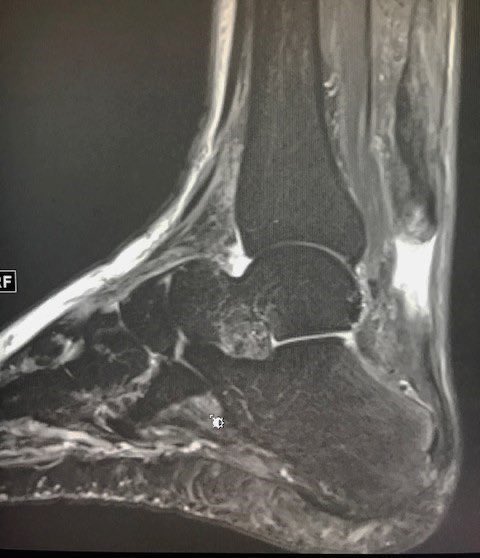

كيف يشخص التهاب #الوتر_العرقوبي ؟

يتم التشخيص عادة من خلال الفحص السريري من قبل الطبيب

و بناء على ذلك يحدد نوع الفحوصات اللازمة:

الأشعة العادية "السينية"✔️

الأشعة الصوتية✔️

أشعة الرنين المغناطيسي ✔️